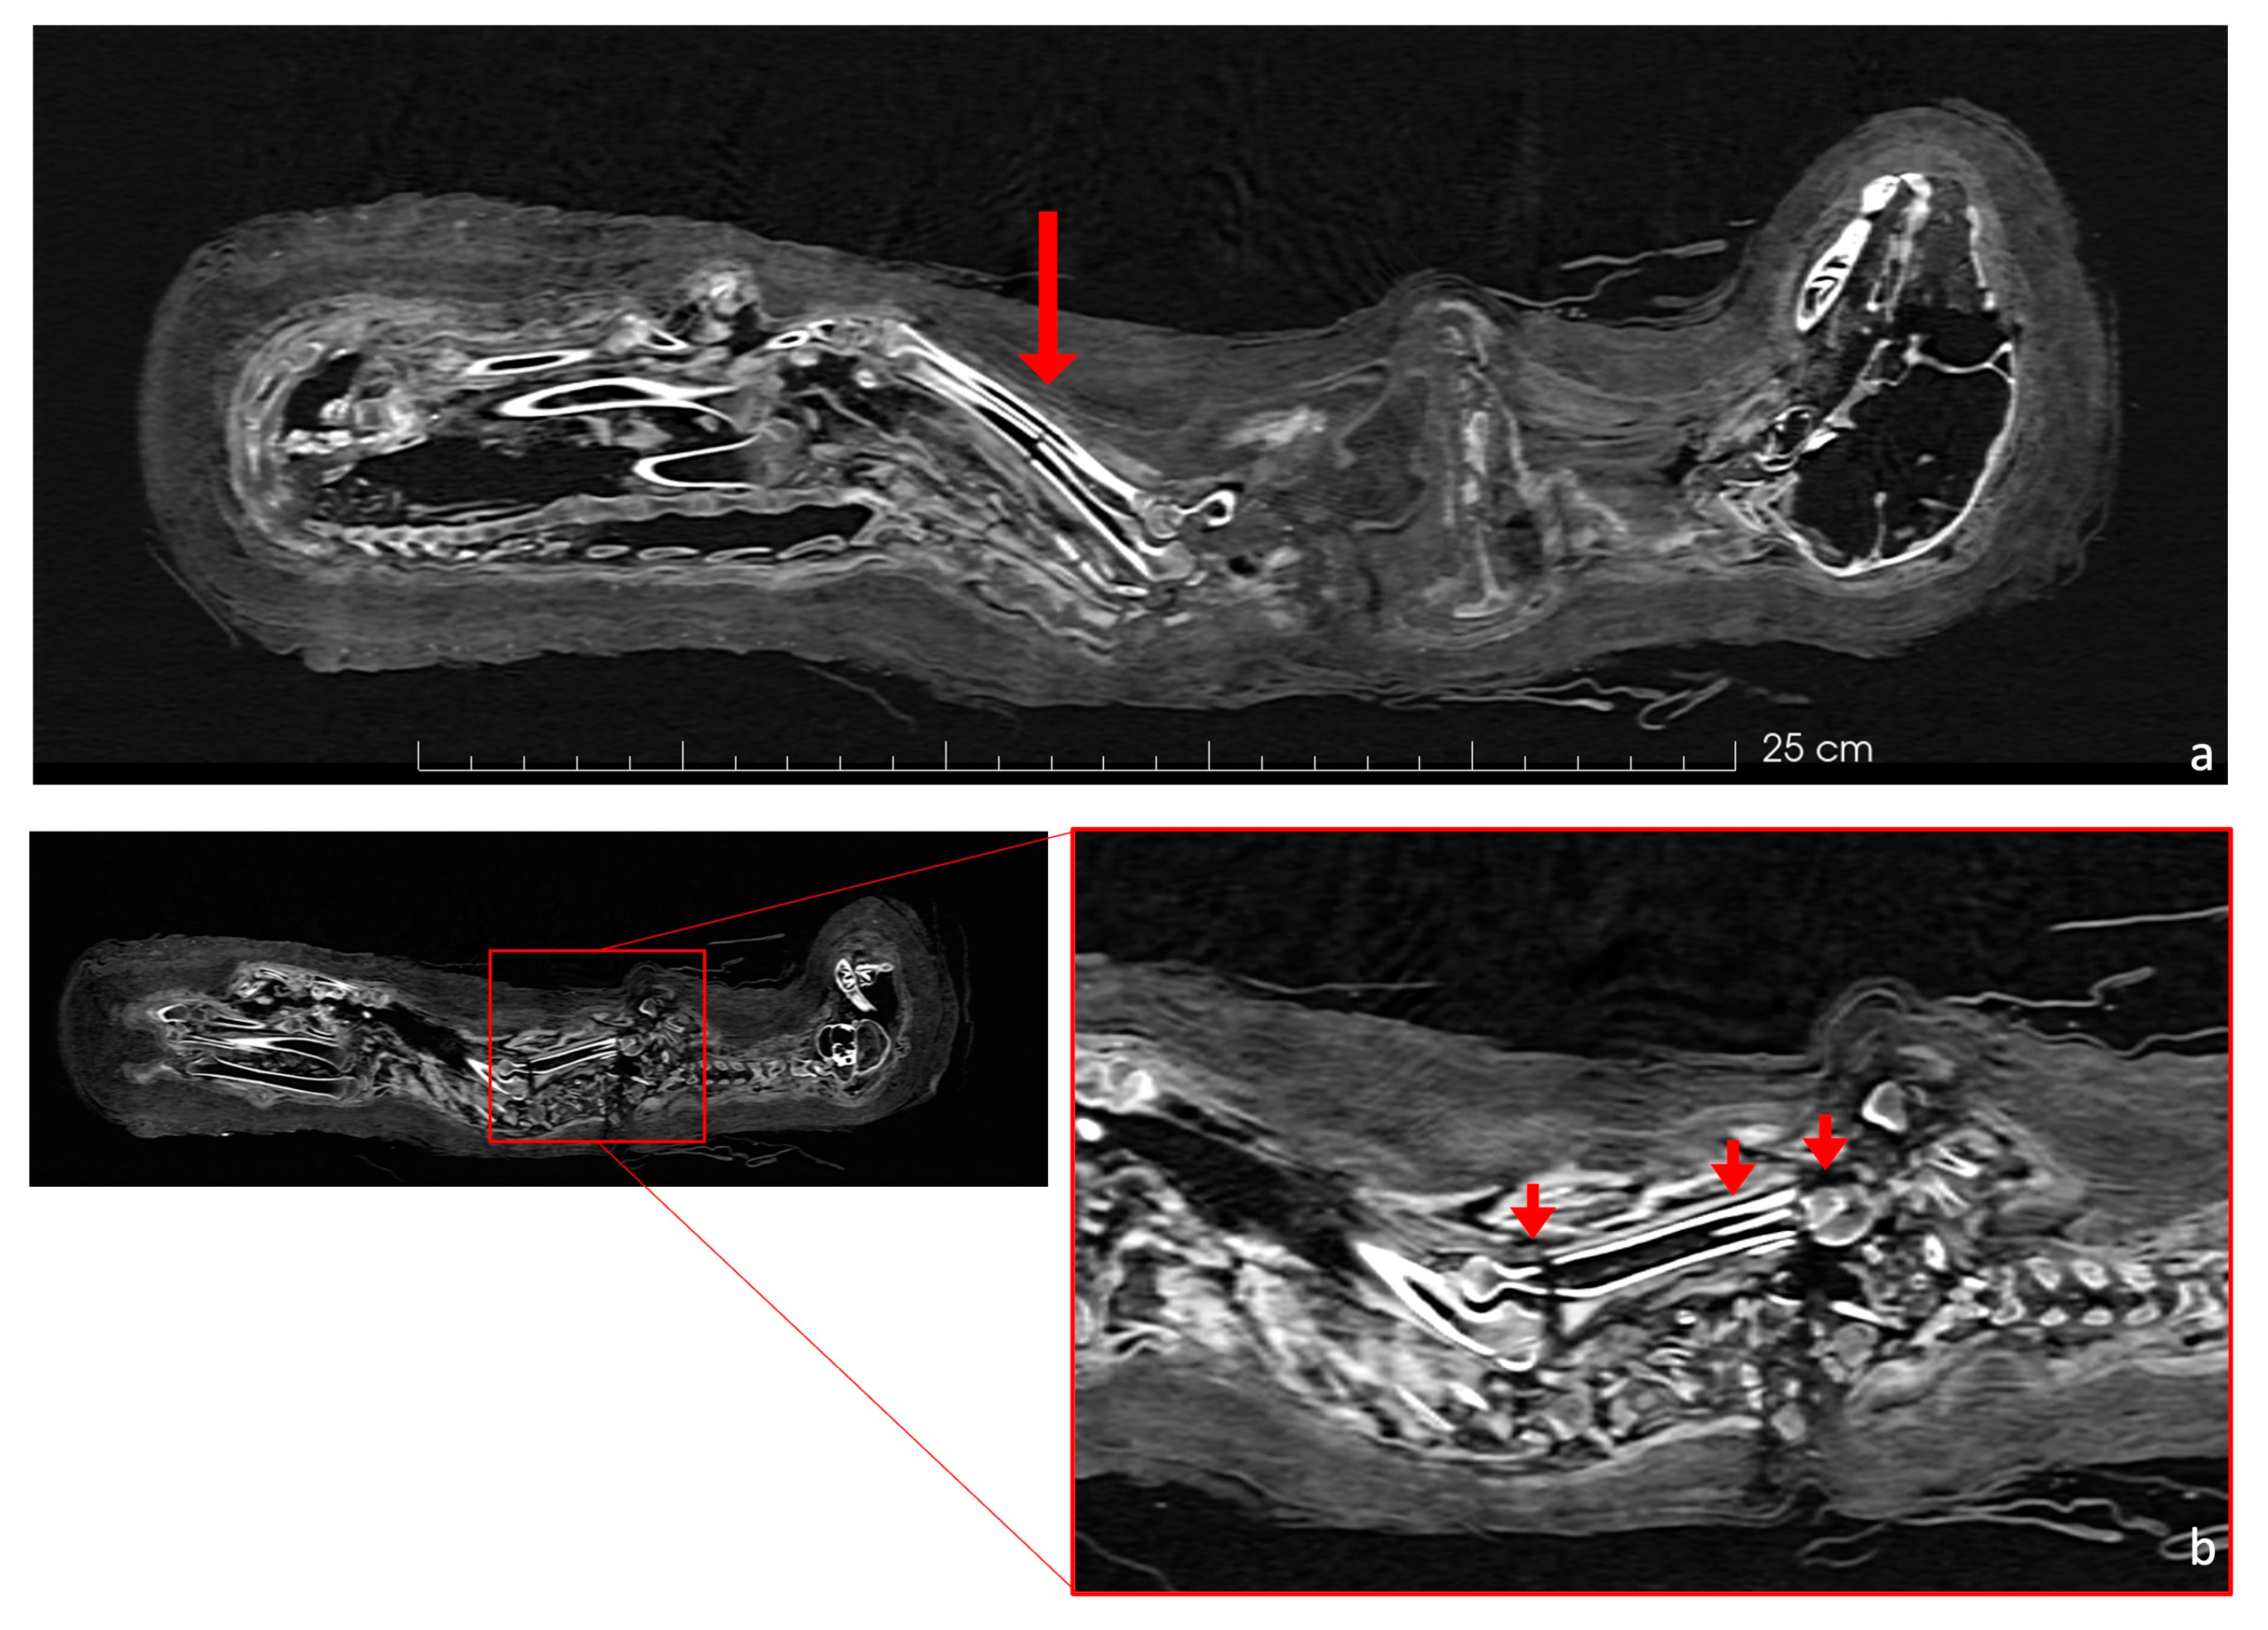

In the hind legs, the femurs’ distal epiphyses were unfused, as were the proximal epiphyses of the tibiae, which appeared to be unfused, with the line between the epiphyses and the shafts being very clear (Figure 4b–e). The proximal epiphysis of the humerus, the ulna, and the distal radius were also not fully developed (Figure 4d,f,g). These provide further evidence of the animal’s age. The epiphyseal status is reported in Table 1.

Figure 4.

(a) The figure presents a coronal view of the right side of the cat’s skeleton. (b) Zooming into the red panel of Figure 4a, it shows the unfused distal epiphysis of the right femur and the proximal epiphysis of the right tibia. (c) Similarly, in the yellow panel, the right proximal ulna physis is open (red arrow). (d) A coronal view of the cat skeleton (left side). (e) Zooming in on the red panel from Figure 4d, this image highlights the unfused distal femoral and proximal tibial epiphyses with a red arrow. (f) Further enlargement (orange panel) within the figure focuses on the incomplete distal epiphysis of the radius. (g) The proximal epiphysis of the right humerus is completely separated.

The scans show that the distal epiphyses of the femurs were unfused, as were the proximal epiphyses of the tibiae (Figure 8). Regarding the forelimbs, the proximal epiphyses of the right humerus and the right ulna were unfused, as well as the distal epiphysis of the right radius. All these findings are an indicator of an immature individual [42,43]. The young age is a problem for its taxonomic identification, as the diagnostic skeletal features are not fully developed and biometry is limited to certain skeletal elements. The distal breadth of the humerus (Bd, following von den Driesch, 1979) is 15.8 mm. The humerus was chosen as the distal epiphyses was already fully ossified. Even if a possible slight further growth of the bone cannot be excluded, the size is in line with the variation of Felis silvestris and looks to be too small for the jungle cat Felis chaus [14]. The size overlaps with that of the sand cat Felis margarita [14], but this species is considered to be much rarer and looks to be uncommon in the zooarcheological record in Egypt [16]. If we hypothesize the attribution to Felis silvestris, common amongst votive mummies [47,48], the individual was almost certainly younger than 9 months [43,44]. Furthermore, the dentition was still composed of deciduous teeth, while the permanent molars were unerupted (Figure 3b) and the fourth premolar of the maxilla was still within the chamber (Figure 3a). Since molars erupt at 5 or 6 months, and the eruption of permanent premolars occurs between 4 and 6 months [45], it is possible to hypothesize that the animal was probably less than about 5 months old at death. This age is very common among cat mummies, as other mummies prove [47,48,50].

Most of the postcranial elements have evident fractures, such as those indicated in Figure 4. The breaks on the limb bones seem to have occurred post-mortem, unlike the fractures on the skull and vertebrae. For example, the proximal part of the humerus is separated and rotated by 90 degrees in relation to the bone’s diaphysis (Figure 6b). The manipulation, embalming process, and positioning of the skeleton may have compromised the structural integrity of the bones, as did its burial and subsequent transport, since there is no evidence for bone repair/growth.